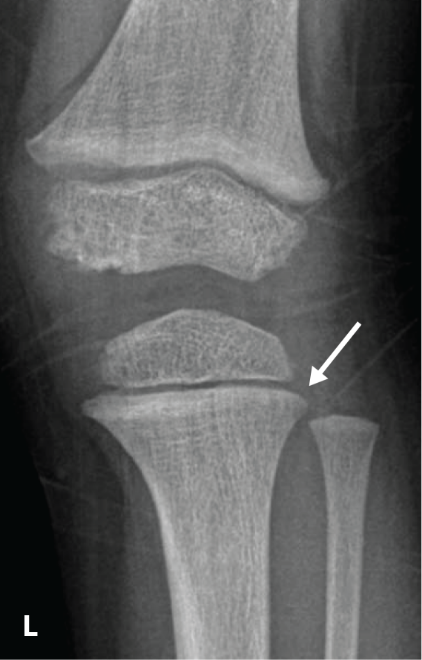

The RSS is a quantitative method that uses radiographs to assess the severity of rickets at the wrists and knees. Originally validated in nutritional rickets, the score is based on the degree of metaphyseal fraying, metaphyseal cupping, and the proportion of the growth plate that is affected. It is a 10-point scale, for which 10 represents the most severe radiographic changes due to rickets and 0 represents the absence of these changes.1

Although the severity and duration of rickets vary considerably between XLH and nutritional rickets, the radiographic features of rickets at the growth plate are similar in the two disorders, which allowed validation of the RSS in XLH. The RSS correlates with serum alkaline phosphatase (ALP) levels, a biochemical marker of rachitic activity, and this scoring system can be used to assess the radiographic response following treatment of nutritional or XLH rickets.

The RSS in XLH has been reported to range from 0 to 4.5; however, despite the smaller RSS range observed in XLH patients, inter- and intra-rater reliability are similar to those reported for nutritional rickets. Patients with XLH who had a baseline RSS ≥1.5 were shown to have more severe hypophosphatemic bone disease, including higher levels of alkaline phosphatase, and greater impairments in clinical outcomes compared with patients who had a baseline RSS <1.5.